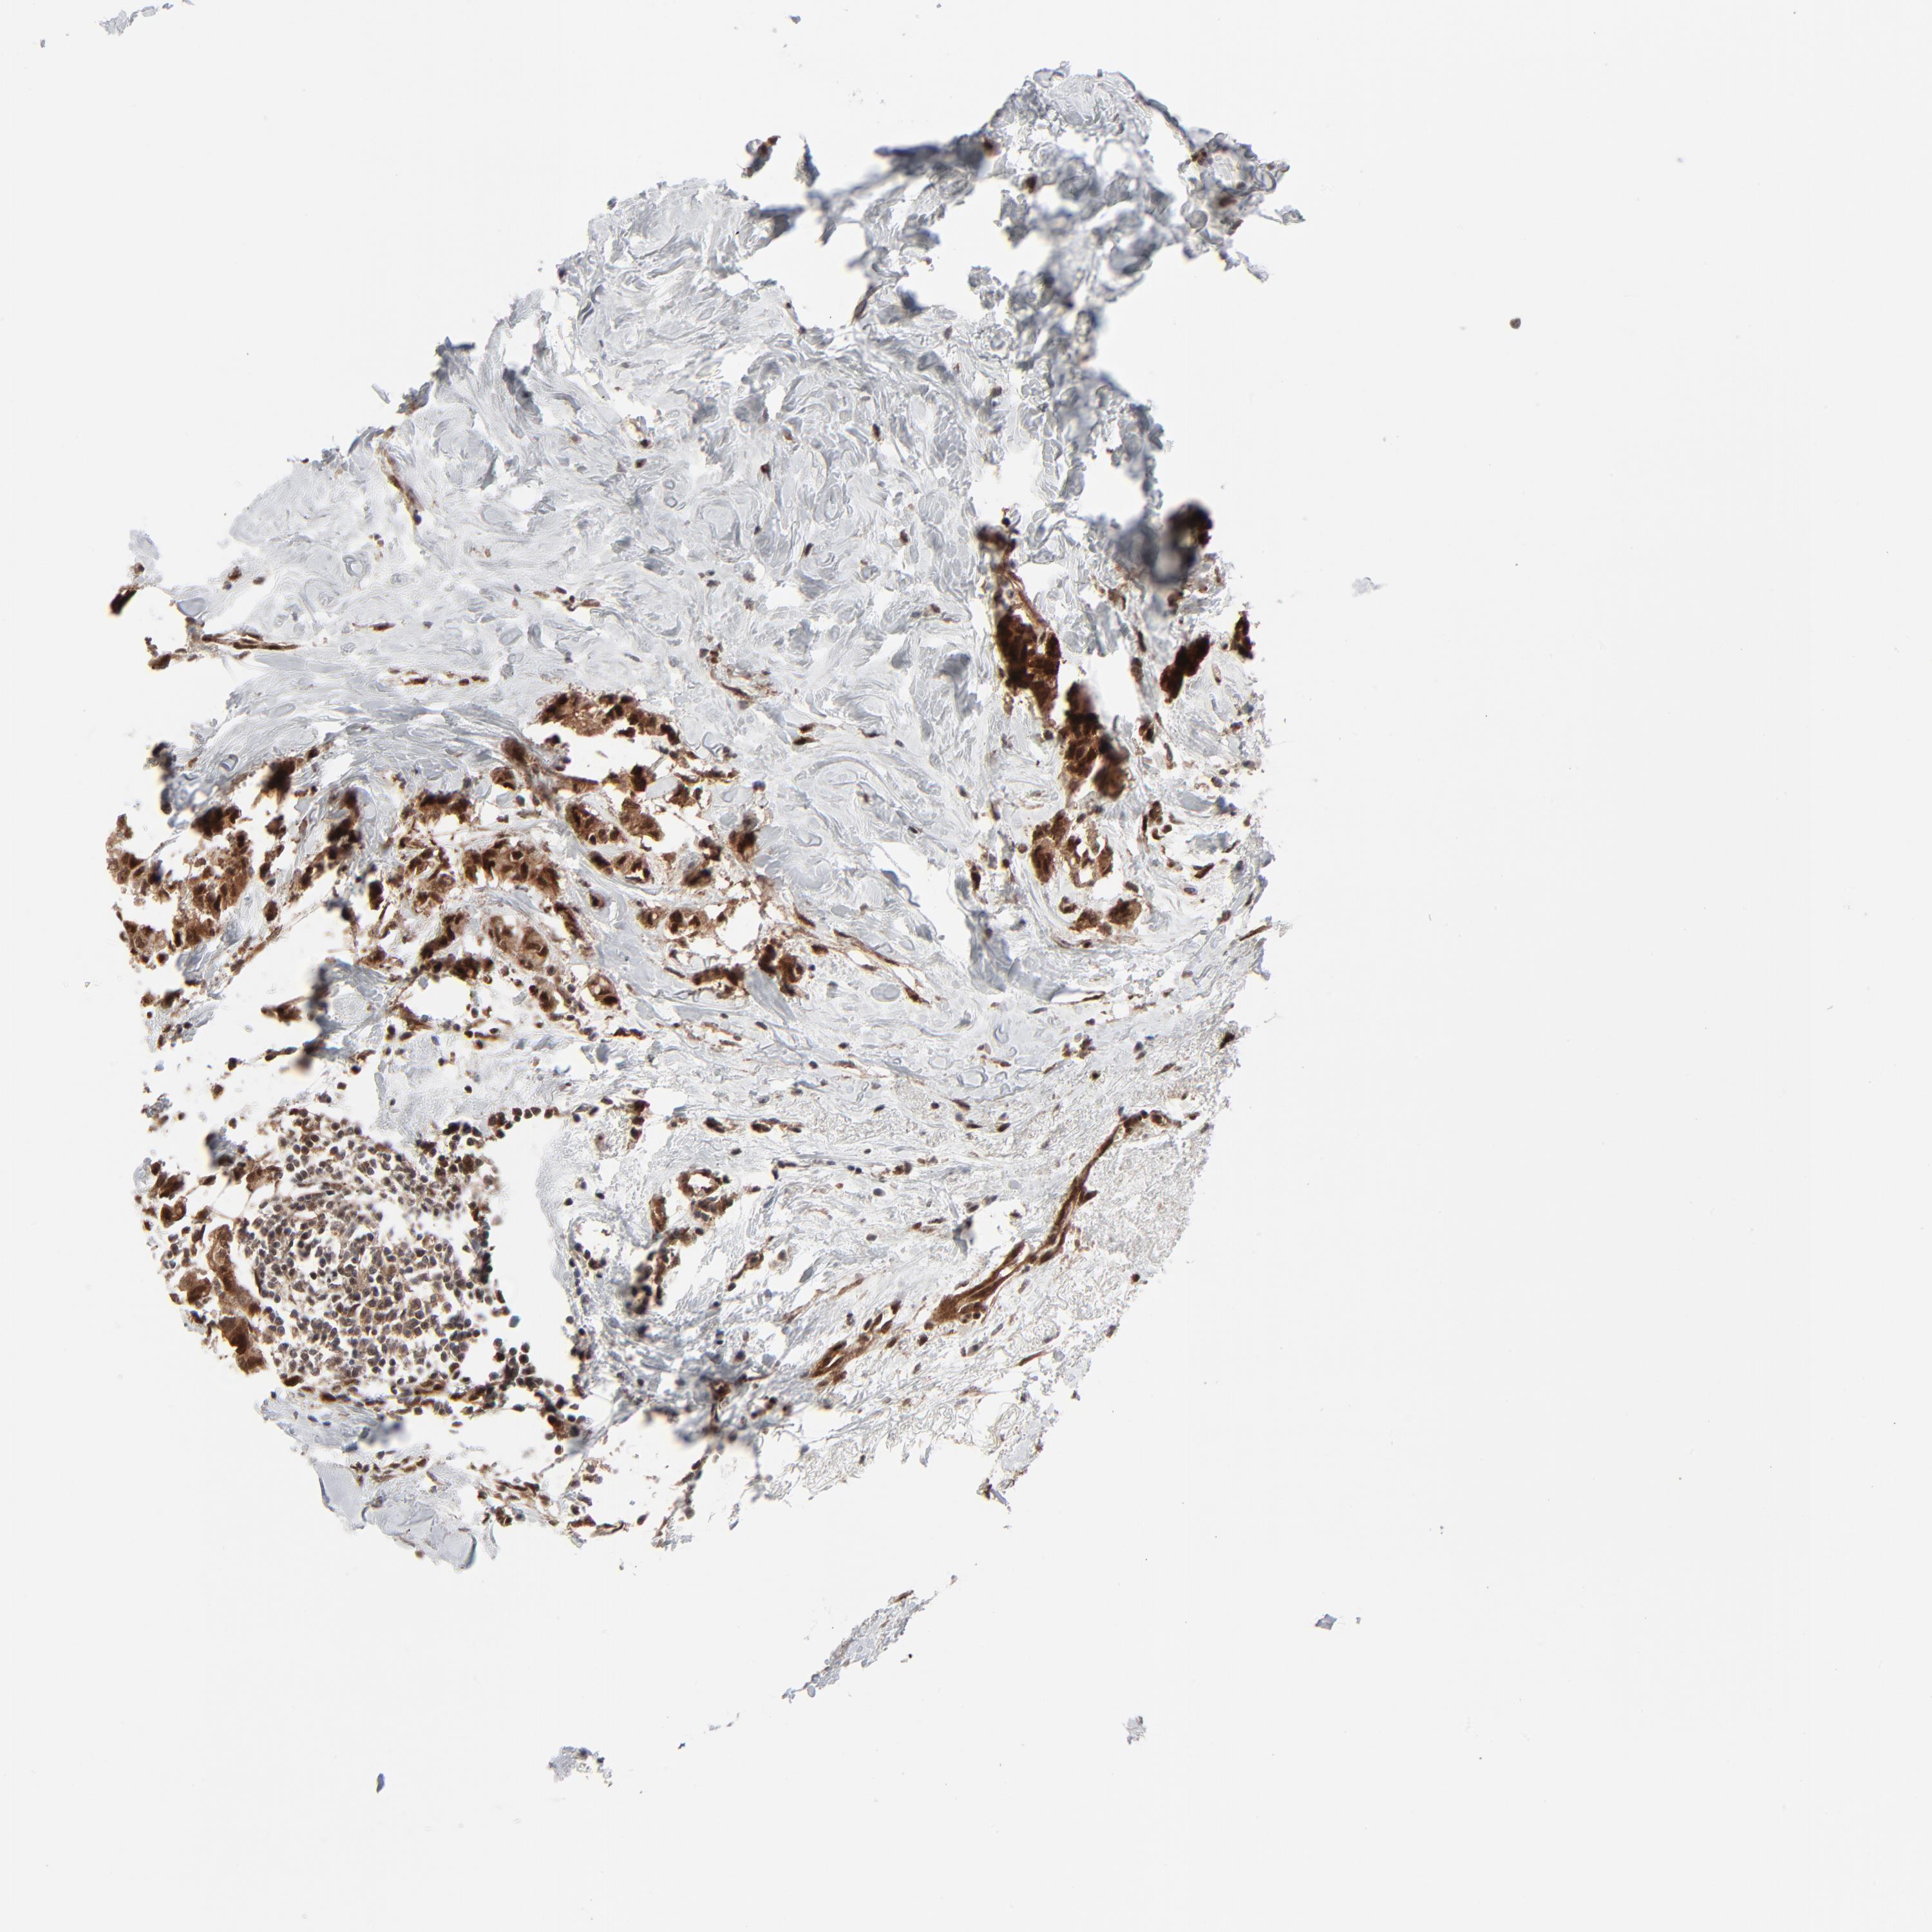

BRCA TCGA BRCA VALIDATION PROTEIN EXPRESSION